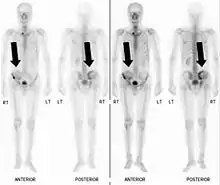

Scintigraphie corps entier avec 99mTc-HDP de la patiente avec une fracture du bras due à une métastase du cancer du sein

La scintigraphie osseuse est actuellement encore le meilleur moyen de diagnostic des métastases osseuses. Ce procédé est relativement sophistiqué, coûteux et soumis à quelques limites diagnostiques[90]. Contrairement à la radio, on peut avec la scintigraphie représenter assez simplement l'ensemble des attaques du squelette[87]. Une scintigraphie osseuse est normalement bien plus sensible pour la détection des métastases osseuses qu'une radio. La sensibilité de la scintigraphie osseuse est assez élevée, avec 95 %. En moyenne, avec cette méthode, les métastases osseuses sont détectées six mois avant leur mise en évidence sur la radio[113]. Par contre la spécificité est substantiellement plus faible[114], car presque toutes les modifications tumorales ou inflammatoires du squelette conduisent à un enrichissement en radiotraceurs dans le voisinage. Le remodelage plus élevé et les processus de réparation dans la bordure des métastases osseuses ostéolytiques conduisent à une accumulation plus élevée du radiotraceur, visible comme un « point chaud » sur l'image de scintigraphie[115]. Un phénomène observable de rebond (flare up) peut être dû à l’augmentation de l’activité ostéoblastique au niveau des zones d’ostéolyse tumorale clinique, dont la colonisation métastatique a été éradiquée par le traitement ; il ne doit pas être confondu avec une progression métastatique, au risque de modifier le traitement de façon intempestive[116]. Dans les métastases osseuses de cancer du poumon ou du sein, la néoformation réactive d'os peut dans de rares cas être absente[117]. Sur la scintigraphie, ceci apparaît alors comme un « point froid », un domaine avec une absorption réduite du radiotraceur[118].